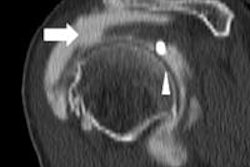

- Knee MRI for patients with anterior knee pain without mechanical symptoms or effusion, unless the patient shows no improvement after an appropriate functional rehabilitation program

- Knee arthroscopy as initial management for patients with degenerative meniscal tears and no mechanical symptoms

Dr. Thomas Magee, managing partner at NeuroSkeletal Imaging in Merritt Island, FL, said that as a radiologist he is not familiar with all of the symptoms that may warrant imaging, but a locking knee is a good indication that an MRI may be necessary.

"Then it is appropriate to order an MRI more quickly [rather] than later, the reason being that physical therapy in those scenarios won't work and may in fact be harmful," he said.